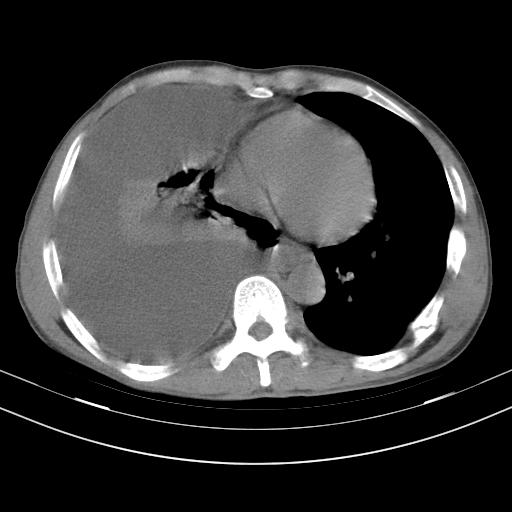

男性,44岁,结核病史多年。现胸闷气短,咳嗽,偶咳血。

右侧胸腔积液

右肺下叶不张

双肺多发结节影最分空洞形成考虑占位不除外结核

双肺陈旧性病变

1、右侧大量胸腔积液伴右肺压缩性膨胀不全,建议抽液治疗后复查 2、两肺继发性tb伴空洞形成。

1)两肺继发性肺结核伴空洞形成,左肺多发性结核球。2)右侧大量胸腔积液伴右肺部分膨胀不全。3)纵隔淋巴结肿大。

吉大一院胸水抽检结果:结核性胸水